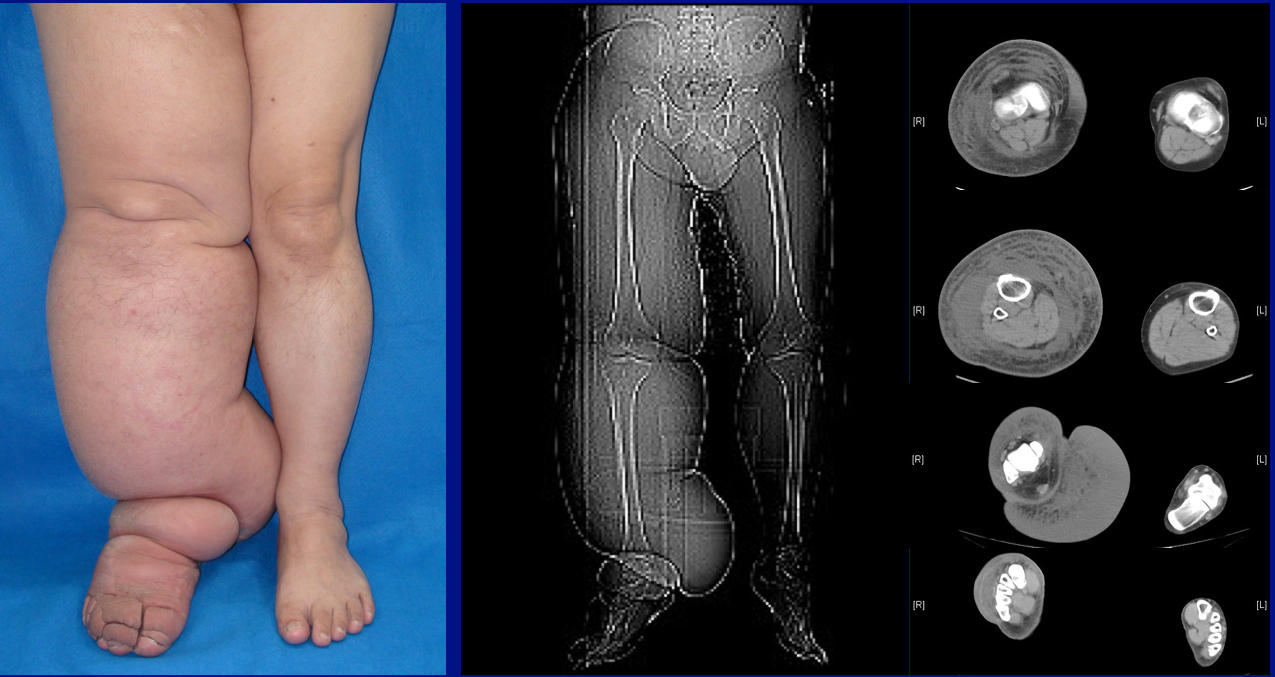

림프부종의 가장 흔한 증상은 연조직 부기(부종)이다. 질환이 진행됨에 따라 부종이 악화되고 피부 변색, 사마귀 모양의 과형성, 과각화증, 유두종증, 진피 비후, 궤양을 포함한 피부 변화가 나타날 수 있다. 또한, 단독으로 알려진 피부 감염의 위험이 증가한다.

4. 1. 증상

진단은 일반적으로 징후와 증상을 기반으로 하며, 다른 잠재적 원인을 배제하기 위해 검사를 사용한다.[30] 정확한 진단과 병기 설정은 관리에 도움이 될 수 있다.[30] 부은 사지는 다른 치료법이 필요한 다양한 상태의 결과일 수 있다. 림프부종의 진단은 현재 병력, 신체 검사 및 사지 측정을 기반으로 한다. 림프관 조영술 및 인도시아닌 그린 림프 조영술과 같은 영상 연구는 수술을 고려할 때만 필요하다.[30] 그러나 치료 지침을 위한 이상적인 병기 설정 방법은 여러 가지 제안된 프로토콜로 인해 논란의 여지가 있다.[31][32]

림프부종은 상지 및 하지 모두에서 발생할 수 있으며, 경우에 따라 머리와 목에서도 발생할 수 있다. 사지 평가는 시진으로 시작하며, 색상, 털 유무, 눈에 보이는 정맥, 크기, 궤양 또는 궤양 유무를 확인한다. 털이 없는 것은 동맥 순환 문제를 나타낼 수 있다.[33] 부종의 경우, 참조를 위해 사지 둘레를 시간 경과에 따라 측정한다. 림프부종의 초기 단계에서는 사지를 올리면 부기가 감소하거나 사라질 수 있다. 손목이나 발목의 촉진은 부종의 정도를 결정할 수 있으며, 맥박 확인을 포함한다. 액와 또는 서혜부 림프절은 부종으로 인해 비대해질 수 있다. 3주 이상 지속되는 림프절 비대는 감염 또는 기타 질병(예: 유방암 수술 후유증)을 나타낼 수 있으며, 추가적인 의학적 치료가 필요하다.[33]

림프부종의 진단 또는 조기 발견은 어렵다. 첫 번째 징후는 영향을 받은 사지에서 무거움을 느끼는 것과 같은 주관적인 관찰일 수 있다. 이는 림프 축적이 경미하고 부피 또는 둘레의 변화로 감지할 수 없는 초기 단계 림프부종의 증상일 수 있다. 림프부종이 진행됨에 따라 결정적인 진단은 일반적으로 영향을 받거나 위험한 사지와 반대쪽 영향을 받지 않은 사지 사이의 객관적인 차이 측정(예: 부피 또는 둘레)을 기반으로 한다. 일반적으로 받아들여지는 진단 기준은 없지만, 사지 간의 200 ml 부피 차이 또는 4 cm 차이(단일 측정 지점 또는 사지 전체의 설정된 간격)가 자주 사용된다. 생체 임피던스 측정(사지 내 체액량을 측정)은 다른 방법보다 더 높은 민감도를 제공한다.[34] SOZO와 같은 장치는 생체 임피던스 분석(BIA)을 사용하여 신체를 통해 전류를 보내고 그 결과 임피던스를 측정한다. 또 다른 방법은 조직 유전율 상수(TDC) 측정으로, Delfin Technology의 MoistureMeterD 및 LymphScanner와 같은 장치에서 사용되며, 마이크로파를 사용하여 조직의 유전 특성 변화를 감지한다. 이러한 혁신적인 기술은 림프부종 감지를 위한 공식 프로토콜의 필수 요소가 되었다.[37]

림프부종은 심각도에 따라 분류될 수 있다(일반적으로 건강한 사지와 비교):[45]

- '''1단계''' (경미한 부종): 팔뚝과 손 또는 다리와 발과 같이 먼 부위가 포함된다. 둘레의 차이는 4cm 미만이며 다른 조직 변화는 없다.

- '''2단계''' (중등도 부종): 전체 사지 또는 해당 부위의 몸통이 포함된다. 둘레의 차이는 4-6cm이다. 함몰 등의 조직 변화가 나타난다. 환자는 연조직염을 경험할 수 있다.

- '''3a단계''' (심한 부종): 림프부종이 한쪽 사지와 관련된 몸통 부위에 나타난다. 둘레의 차이는 6cm 이상이다. 각화, 각화증, 낭종 또는 누공과 같은 상당한 피부 변형이 나타난다. 또한 환자는 연조직염의 반복적인 공격을 경험할 수 있다.

- '''3b단계''' (거대한 부종): 3a단계와 동일한 증상이 나타나지만, 둘 이상의 사지에 영향을 미친다.

- '''4단계''' (거대한 부종): 림프부종의 이 단계에서는 림프관의 거의 완전한 폐쇄로 인해 영향을 받은 사지가 거대해진다.